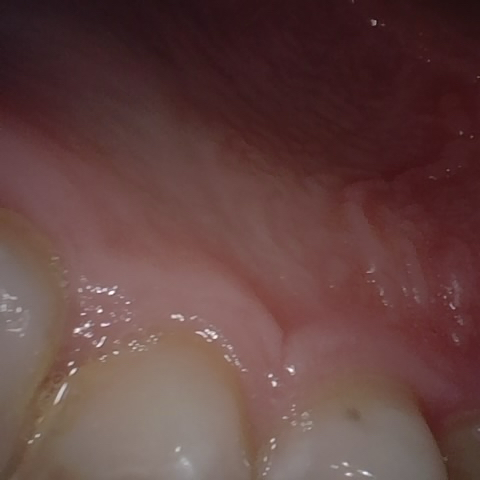

Annotated as "Good"